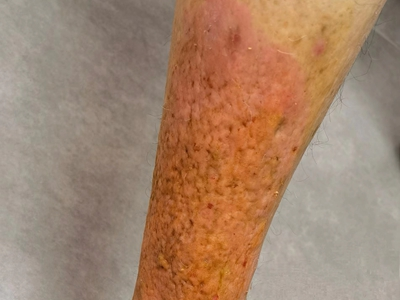

播散性神经性皮炎皮损呈苔藓样改变,瘙痒阵发性发作,病程慢性易反复。皮损好发于头部、四肢、腰部等处,分布广泛而弥散,既有疏散性淡红色或褐色扁平丘疹,也有大小不一苔藓样斑片;有的皮损可沿抓痕呈条状排列,自觉阵法性剧痒,夜间加重,患者常因此失眠而表现情绪烦躁。